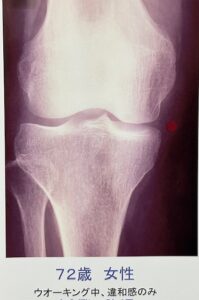

72歳、膝に違和感を感じて来院。

レントゲン きれいです。

早めに受診された方。運動療法で軽快。